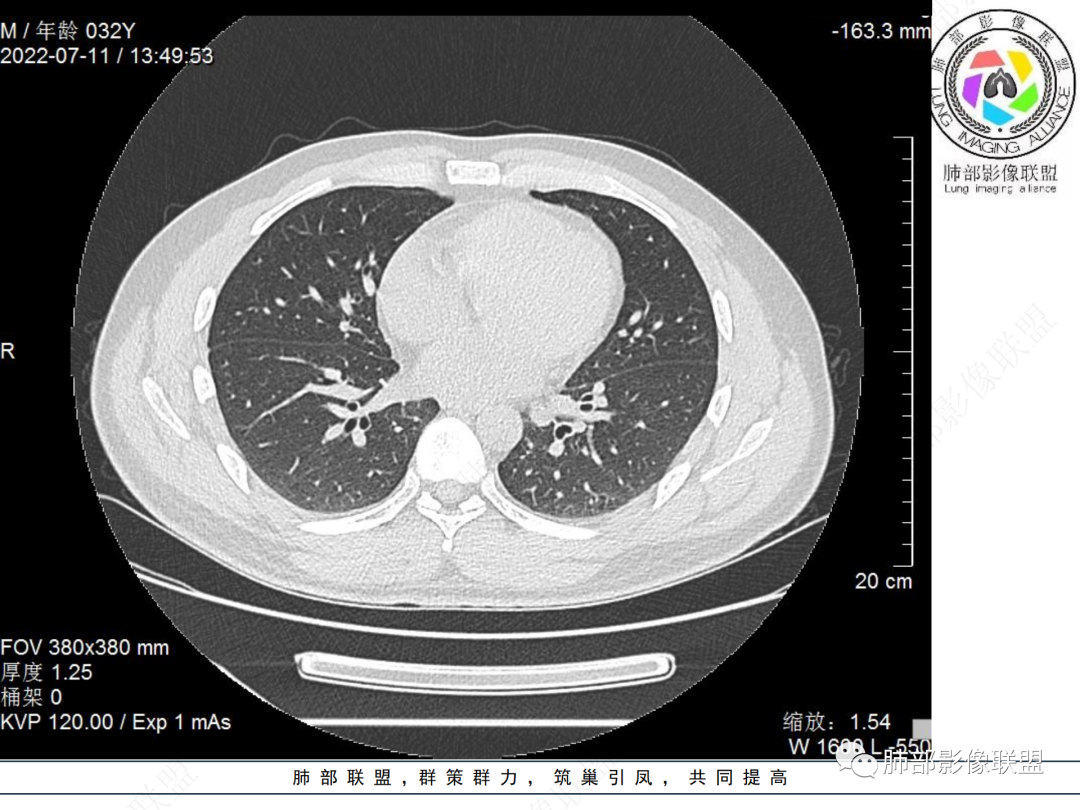

左肺下叶后基底段开口处结节,边缘光滑清楚,没有增强扫描,年轻男性患者痰血三天,考虑1.良性病变:腺瘤、错构瘤、平滑肌瘤

2.恶性:类癌、粘液表皮样癌。

左肺下叶外后基底段气管内见结节状影,边缘部分清晰。考虑错构瘤,待排恶性病变。

左肺下叶气管内外占位病变,咯血病史,考虑类癌,粘表待排。

青年男性,左肺下叶后基底段支气管开口软组织结节,边缘光整,气管镜提示质软,易出血,考虑类癌

左肺下叶后基底段开口处结节,边缘光滑清楚,年轻患者考虑鳞癌或腺样囊腺癌

左肺下叶气道腔内占位,远端无花花草草,疾病谱:鳞,类癌,粘表,腺样囊腺癌,小,无增强,不好判断,临床咯血,选类癌。

大支气管腔内结节,考虑类癌

左肺下叶后基底段开口处结节影,边缘光滑,患者年龄较小,首选类癌

男性,咳血左肺下叶支气管腔内结节影,没有阻塞性炎症,考虑类癌,鳞癌

年轻男性,支气管内结节,首先类癌

左肺下叶后基底段开口处腔内见壁结节,花生米样,宽基底,补充增强及矢状位重建,确定我无向壁外突破浸润生长,另见强化的特点,临床触之易出血,类Ca可能性大。

年轻男性,支气管腔内占位,边缘尚平整,年轻人,首先类癌,鉴别错构

年轻男性,咳血,左肺下叶后基底段支气管腔内结节,边缘光滑,首先考虑青年三件套,类癌大于粘液表皮样癌,支气管镜质软,触之易出血,鉴别血管瘤,平滑肌瘤

左肺下叶后基底段开口部结节,密度较均匀一致,边缘较光整,目测密度偏低,支气管镜示:质软、触之易出血,考虑恶性,类癌。

支气管腔内结节,有蒂与支气管壁连接,考虑良性病变可能性大,支气管错构瘤 血管瘤一类的

左肺下叶后基底段支气管腔内结节,有蒂,容易出血,先考虑良性病变,肉芽组织型血管瘤,与类癌鉴别。

青年男性,左肺下叶后基底段支气管开口软组织结节,边缘光整,气管镜提示质软,易出血,考虑恶性类癌

左肺下叶后基底段开口处结节影,边缘光整,年轻患者,伴咯血,考虑鳞癌,类癌不能排除